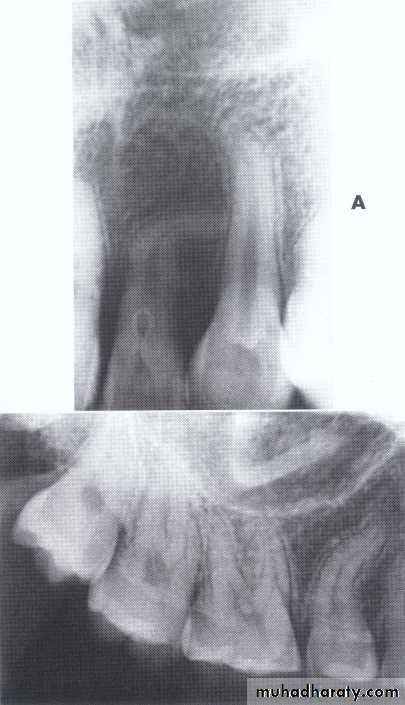

Dilaceration of the crown

specimenX-Ray

Dilacerated root. The apical portion of the root is bent buccally or lingually into the plane of the central ray. Note the halo in the apical region, produced by the PDL

space (arrow).